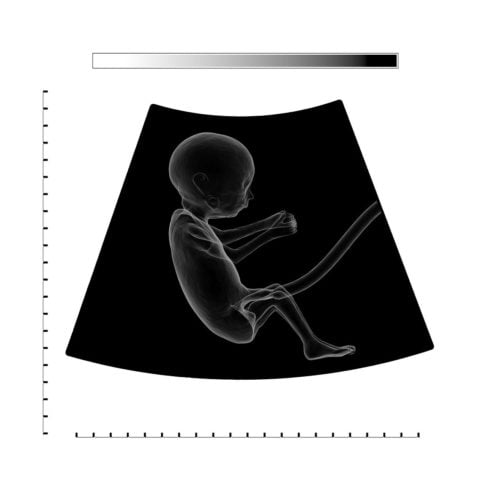

Mulher passa mais de 50 anos com feto calcificado na barriga